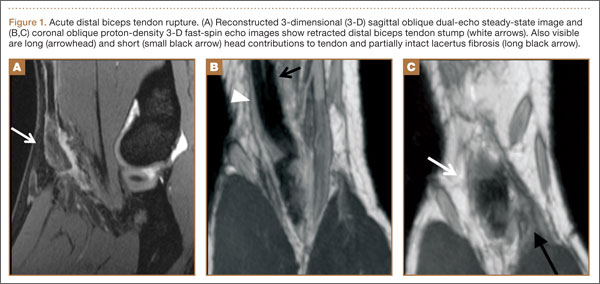

Physical examination revealed distortion of the biceps with a palpable defect in the right elbow consistent with a complete biceps tendon rupture. This was confirmed on MRI, which showed avulsion of the distal biceps tendon from its insertion on the radius. There was 4 cm of proximal retraction of the tendon, which was kept at the level of the joint line by a partially intact lacertus fibrosis (Figure 1).